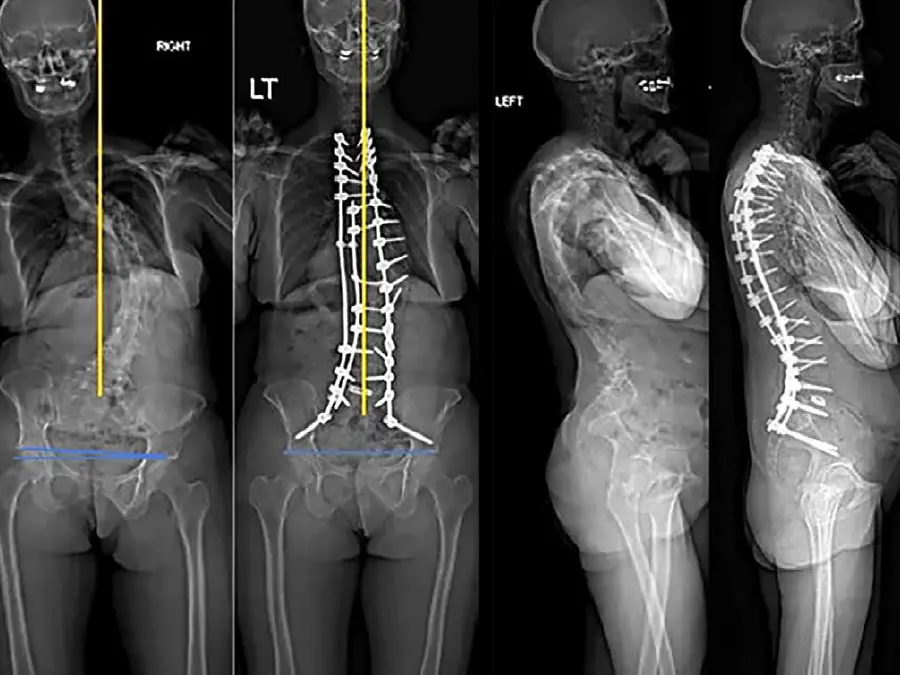

Improving Coronal Alignment Post Spinal Deformity Surgery

Orthopedic spine surgeons from Och Spine at NewYork-Presbyterian/Columbia developed a novel intraoperative method to improve coronal alignment after surgery for complex spinal deformities. This new approach offers two distinct advantages: it provides an intraoperative target and it accounts for lower extremity factors (leg length discrepancy and pelvic obliquity) using EOS imaging. Columbia physicians conducted a recent study of the technique, which was the first study to quantify lower-extremity compensation in the coronal plane for adult spinal-deformity surgery. The team is planning follow-up research to further study the association between this method and patient-reported outcomes, complications, and reoperations.

Preop and postop EOS films of patient who underwent adult spinal deformity surgery. Preop films show coronal malalignment with lower extremity compensation. Postop films demonstrate well-aligned spine in sagittal and coronal planes with resolution of lower extremity compensation